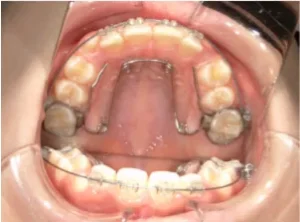

toshi_02_04